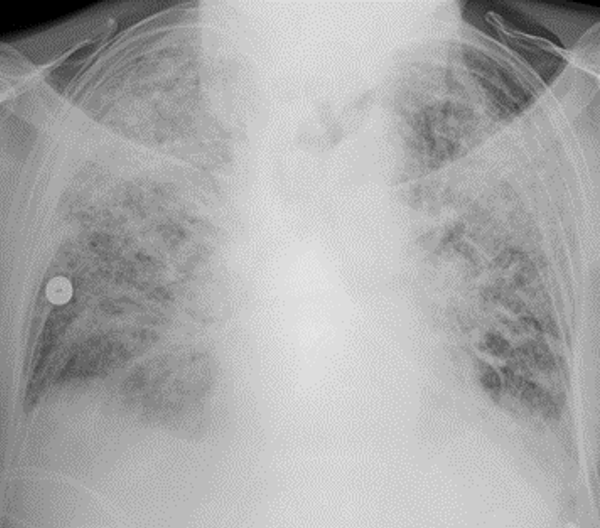

Een shocklong of ARDS

Gebleken is dat als patiënten ernstig ziek worden van COVID-19 dit meestal gebeurt in de tweede week van de besmetting. De koorts neemt progressief toe en vaak ontstaat een ernstige ontstekingsreactie in de longen die hyperinflammatoire shocklong of ARDS – acute respiratory distress syndrome -genoemd wordt. Hierbij treedt lekkage van de longblaasjes, waar de gaswisseling plaatsvindt, op waardoor de ademhaling ernstig bemoeilijkt wordt. Beademen wordt veelal noodzakelijk en organen kunnen uitvallen vanwege een tekort aan zuurstof.